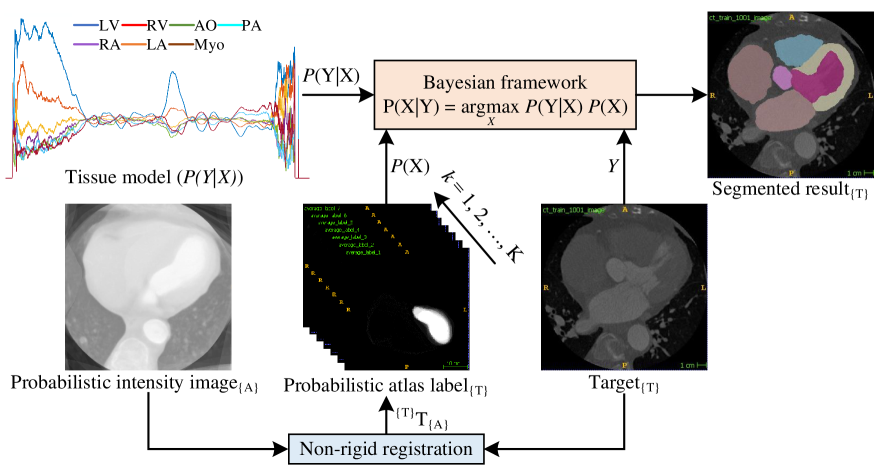

Probabilistic Atlas-based Segmentation (PAS)

In our propsoed PAS framework, we define the actual moving labels as and the target fixed image as , where the components of and are prepared by a spatial location expressed by , wherever is the simplistic rectangular grid index . Let us considering that , , and are the sample realizations of label image, intensity image, and probabilistic label, respectively, where is the total voxel number. Example space of is indicated by , where . The probability atlas is -vector , where all the ingredient corresponds to expectation of -different heart substructures. The prior probability for all voxels can be expressed as .

The hindrance comprises determining the label that adequately illustrates the provided observation according to any loss function. As a decision rule, we chose MAP (maximum a posteriori) and the formula for the realization of estimating of as . The posterior probability () can be written as the multiplication of probability distribution (), also named tissue model [52, 37], and prior probability (), according to the Bayes theorem. is defined by signal intensity tissue models immediately formed from the scans and hand-operated segmentation of the data set. An intensity value’s histogram is constructed for each heart substructure considering the given volumes’ voxels, which belong to it, using hand-operated segmentation. In this work, we estimate the probability distribution of the given image for the provided appropriate segmentation from training data. Algorithm 1 shows detail process of estimating using the number of bins () for the histograms as .

Fig. 3 exhibits an illustration of the Bayesian voxel classification algorithm consolidating the application of the probabilistic atlas of the WHS.

Besides, the probabilistic atlas gives the probability distribution once it has been mapped onto the target space employing the corresponding registration method utilized in its creation.